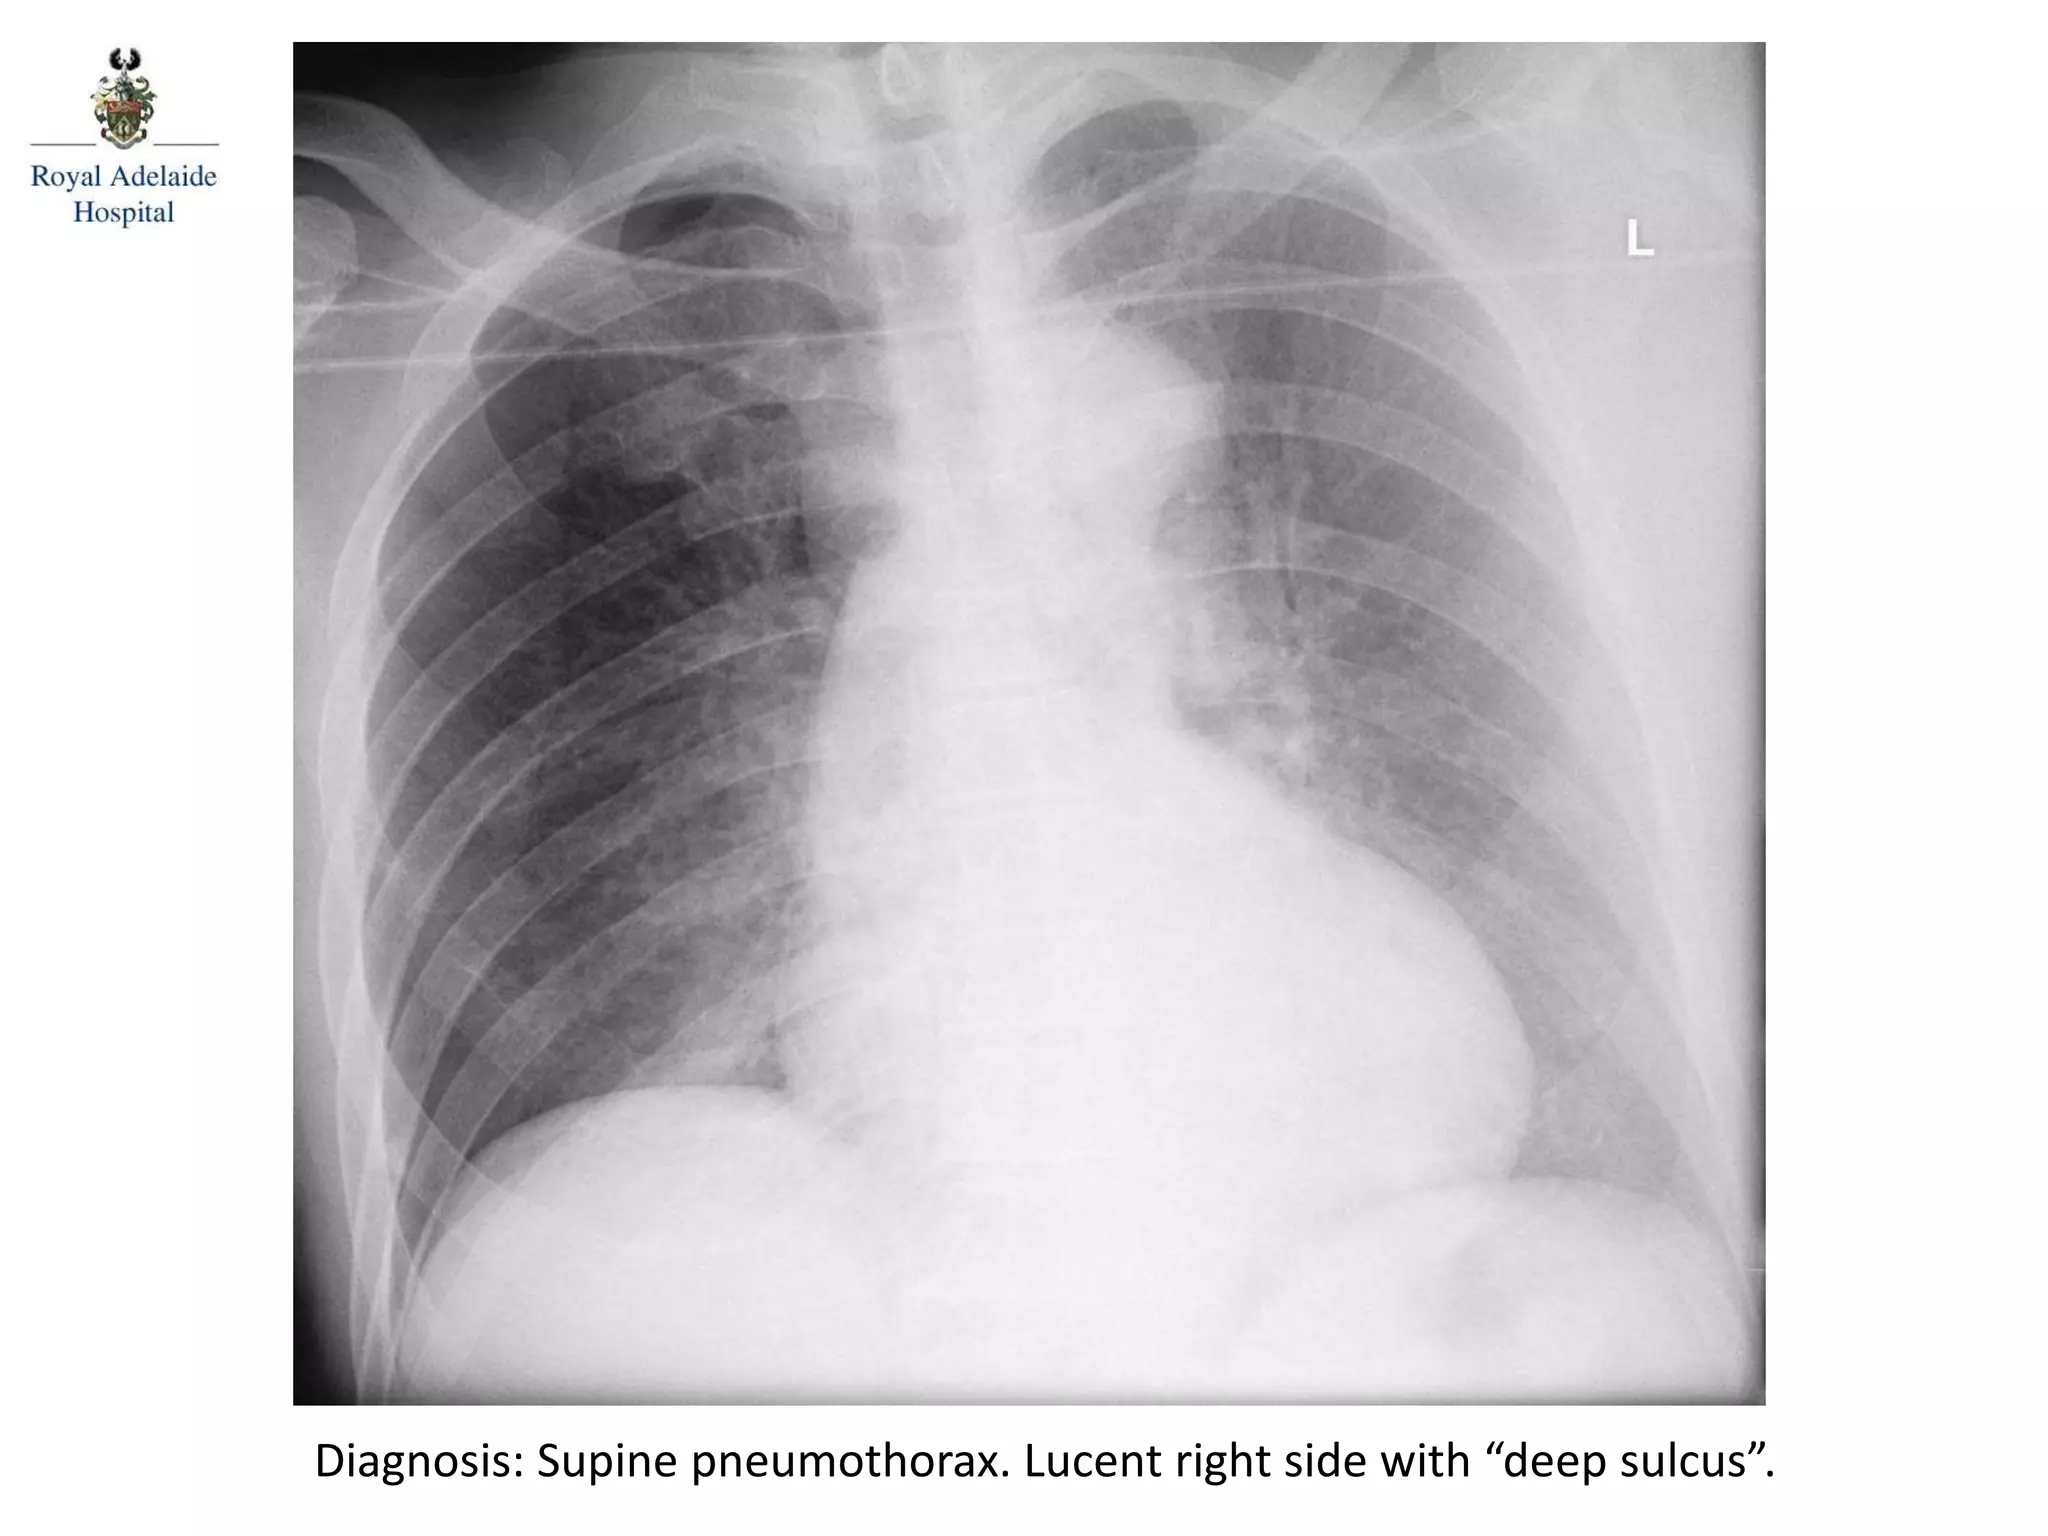

Diagnosis: Supine pneumothorax. Lucent right side with “deep sulcus”.